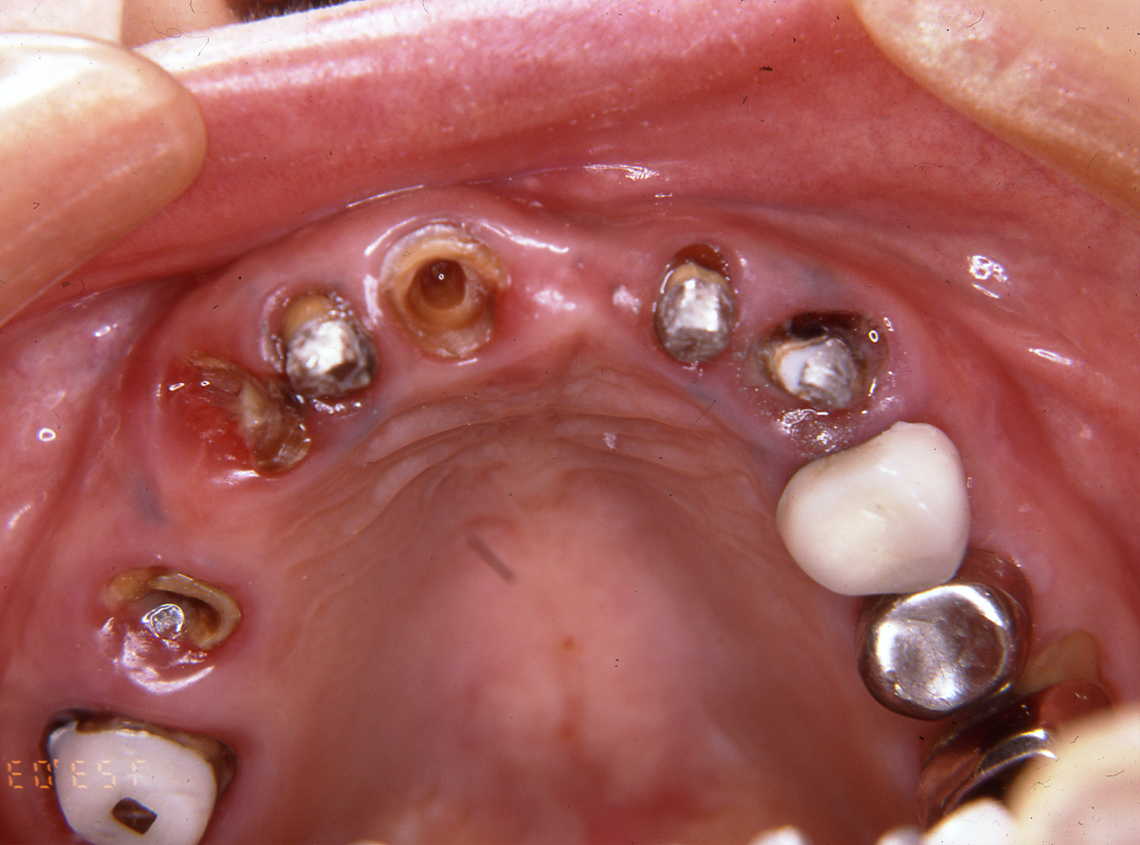

フルマウス治療17年間経過症例

患 者 : S.K様 女性

主 訴 : 補綴物破損、義歯不適による咀嚼障害のためインプラント治療希望

初診日 : 2003年07月11日

1.初診時(2003年)

4.最終補綴物装着(2008年)